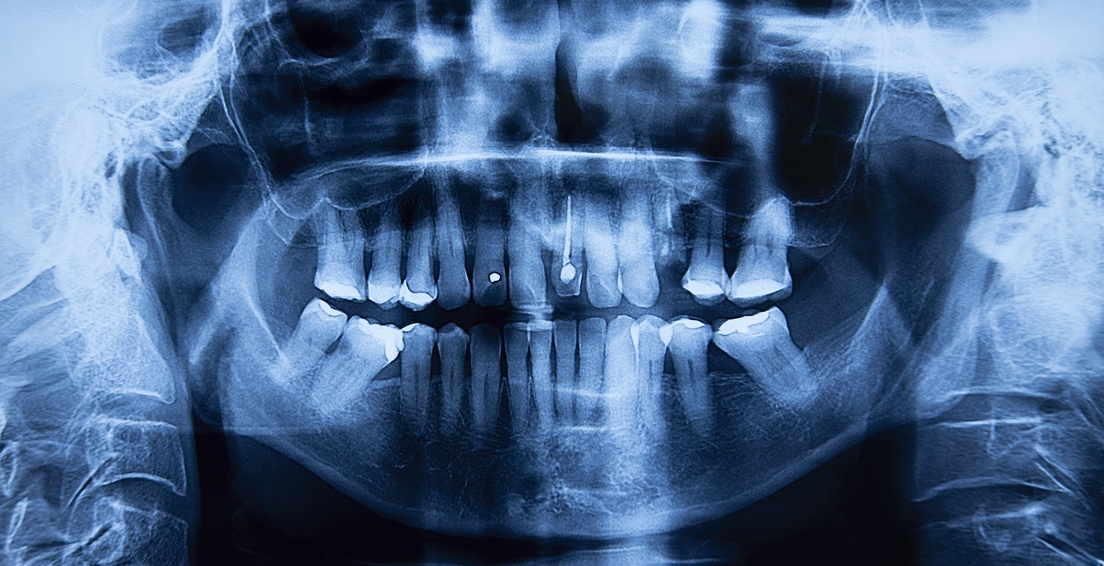

La ortodoncia es uno de los tratamientos más comunes en caso de una mordida imperfecta. Hoy en día, las opciones, tanto en materiales como en métodos, son más diversas que en el pasado y dependen del tipo y gravedad de la maloclusión, así como de otros factores individuales. Los apliques dentales o 'brackets', así como los alineadores, son una solución de eficacia comprobada. Ambos ejercen una presión gradual sobre los dientes, moviéndolos hacia una posición adecuada.

Estas opciones no son las únicas y se centran principalmente en la alineación dental, no en la posición de la mandíbula. En ese caso, podría requerirse de procedimientos quirúrgicos que impliquen la reposición quirúrgica de la mandíbula. "También pueden realizarse procedimientos periodontales o restaurativos para corregir problemas de encías o dientes que estén afectando la mordida", indica la clínica dental española Cristina Viyuela.